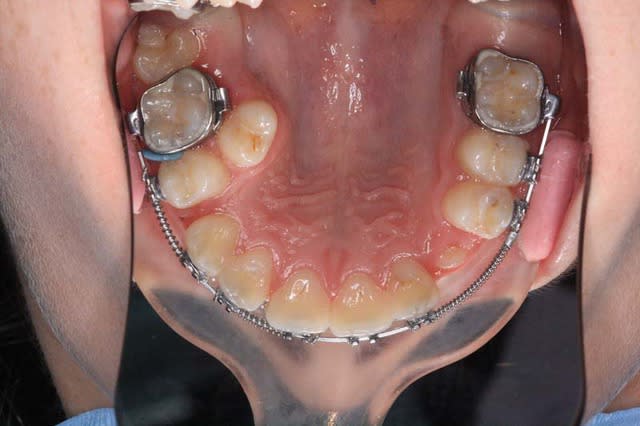

Voici, par exemple, un cas en fin de TTT.

+ Bjc.

Img 1 qmasah - Eugenol

Img 2 vtedrr - Eugenol

Img 3 zxbzaf - Eugenol